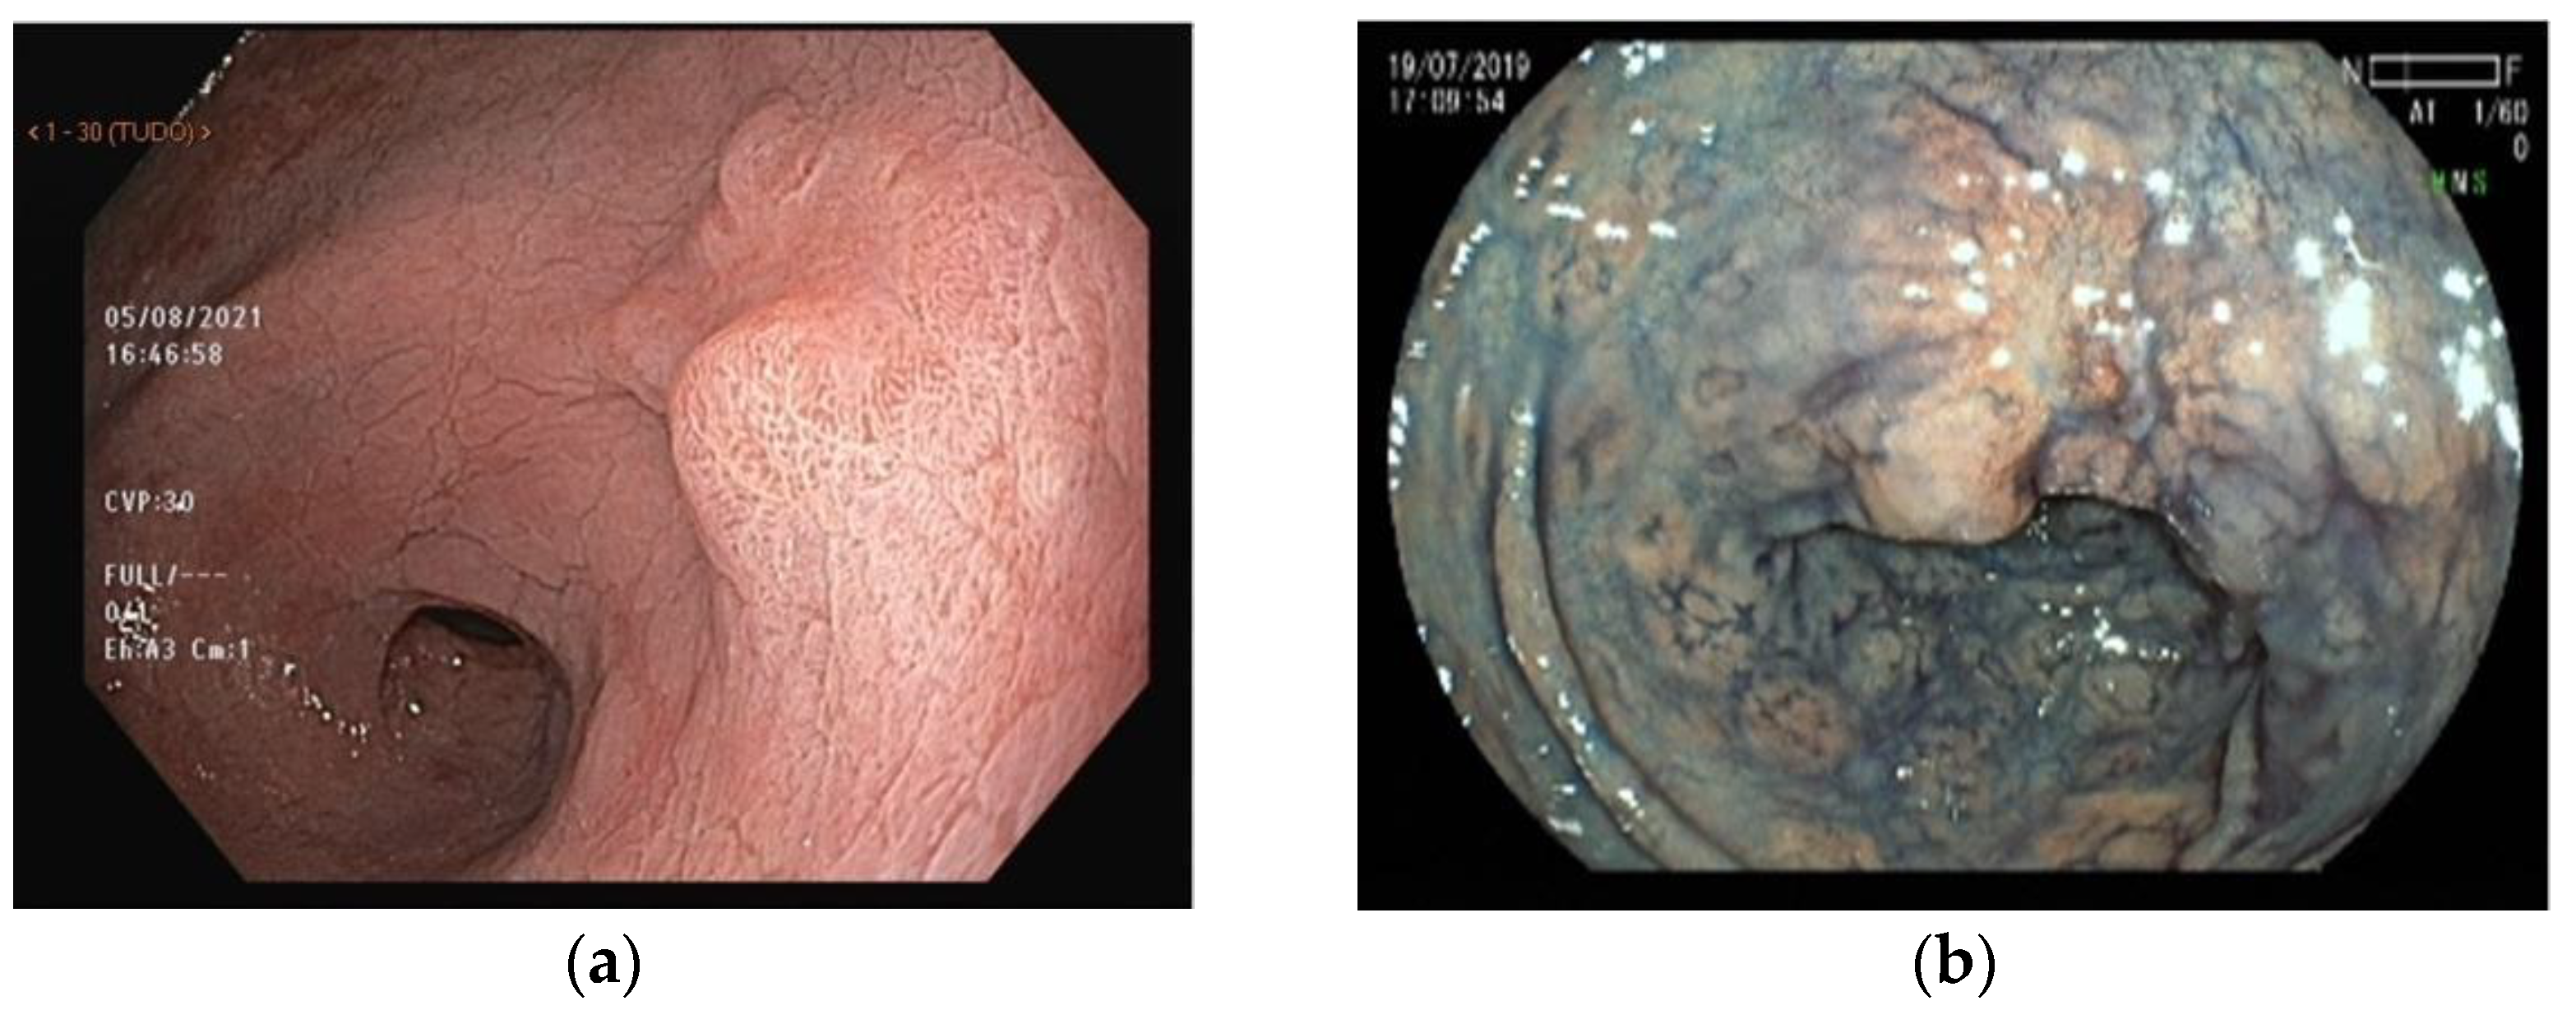

4. Chromoendoscopy

4.1. Acetic Acid

5. Virtual Chromoendoscopy

6. Magnifying Endoscopy